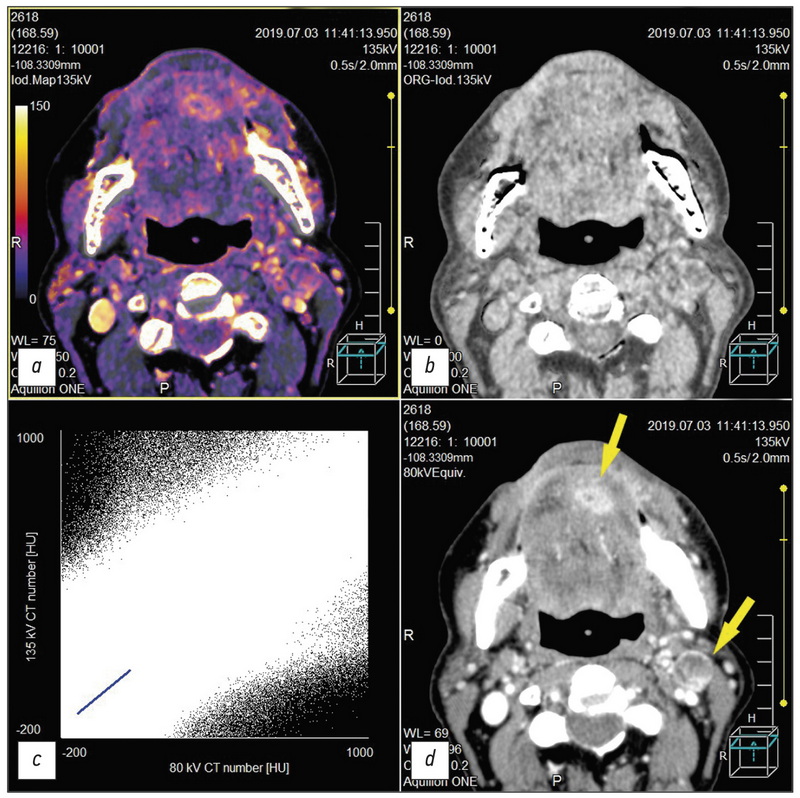

Двухэнергетическая компьютерная томография рака головы и шеи

Аннотация

Выполнен обзор публикаций по диагностике рака области головы и шеи методом двухэнергетической компьютерной томографии (ДЭКТ); изучены результаты качественного и количественного анализа данных, полученных методом ДЭКТ с внутривенным контрастированием при опухолях данной локализации; показана важность построения йодных карт для получения дополнительной диагностической информации; описаны аспекты улучшения визуализации орофарингеальной области на фоне артефактов от стоматологических имплантатов. Ряд приведённых в статье научных работ освещает современное состояние вопроса и роль постпроцессинга «сырых данных» ДЭКТ, получения диапазона монохроматических изображений опухолевых и иных патологических изменений области головы и шеи, в том числе сравниваются ДЭКТ с внутривенным контрастированием и рутинная компьютерная томография с точки зрения уменьшения лучевой нагрузки на пациентов, в частности за счёт получения в ходе постобработки виртуальных нативных диагностических изображений из контрастной серии объёмов ДЭКТ. Обзор, помимо последних актуальных научных данных, включает также ссылки на работы по истории развития ДЭКТ как метода. Кратко изложены физические принципы, лежащие в основе ДЭКТ, и перспективы развития метода.

343-355